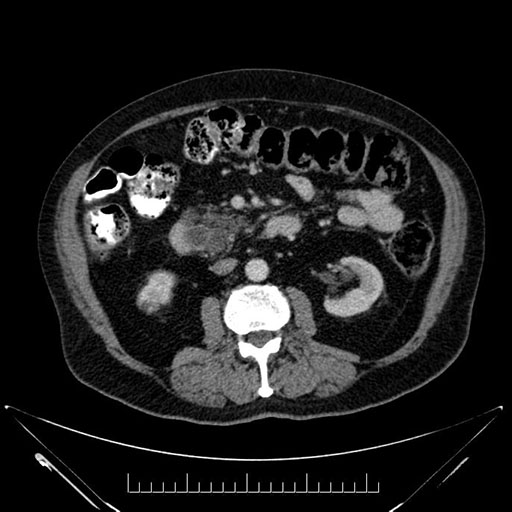

Whipple (pancreaticoduodenectomy) [case 7]

Imaging Analysis

Look through the patient's CT scan to identify any areas of concern for the necessary procedure.

Based on your CT findings, which issue(s) would give reason for "planned slowing down moment(s)" in this case?

Considering a standard Whipple procedure, what step(s) of the operation would you do differently in this case?